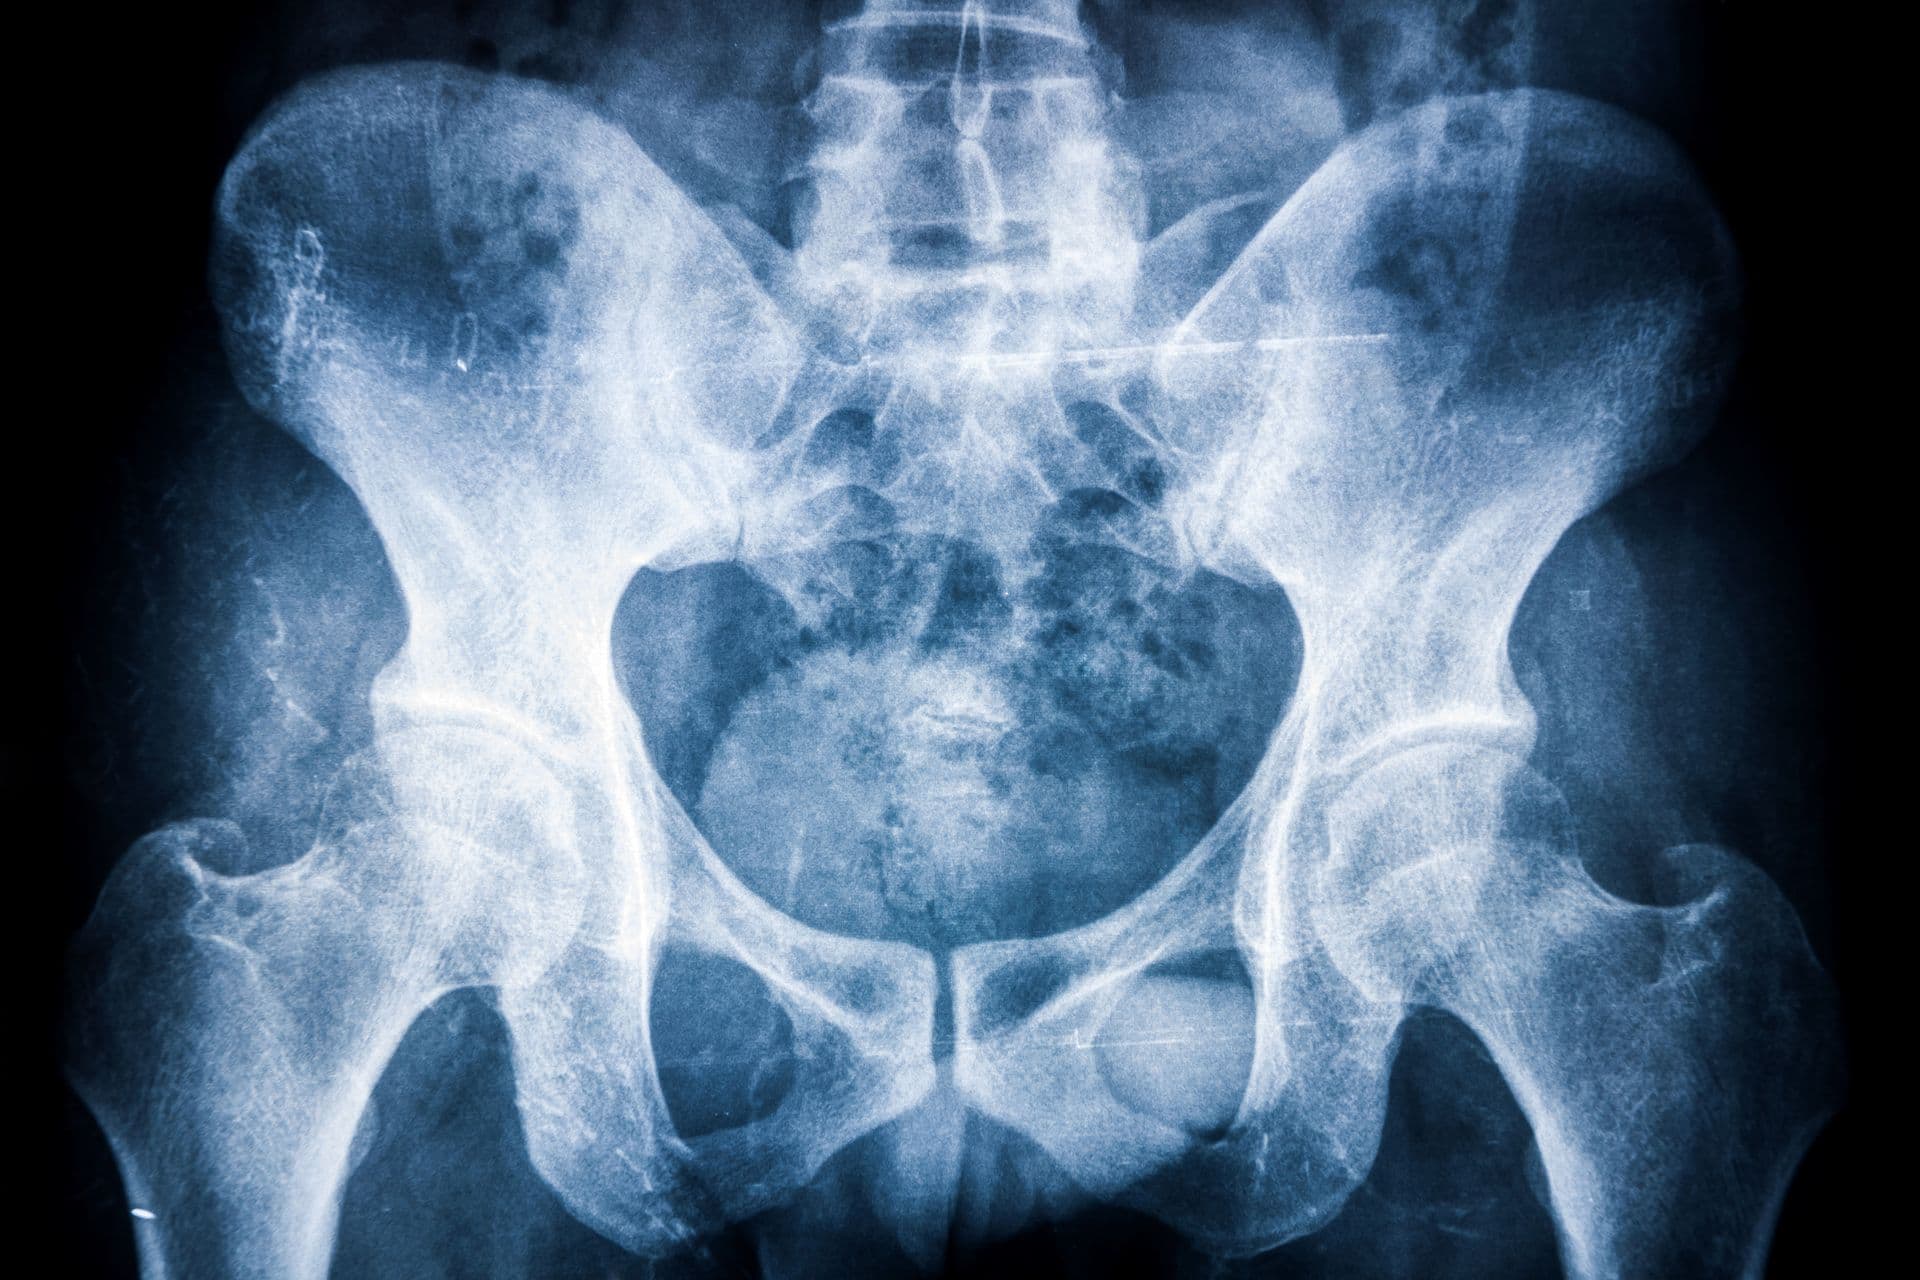

A Bechterew-kór (spondylitis ankylopoetica) elsősorban a gerinc ízületeket, illetve a medencecsont és a keresztcsont között található ízületeket érintő gyulladásos betegség, amely idővel akár az alsó végtagi ízületeket is érintheti. Milyen tünetek utalnak a degeneratív megbetegedésre, és hogyan történik a Bechterew-kór gyógyítása? Az alábbiakban erről olvashatsz!

A spondylitis latin eredetű szó, melynek jelentése: csigolyagyulladás. A gyulladás jellemzően a gerincoszlop alsó végétől indul, és általában fiatal felnőttkorban vagy 25 éves kor környékén jelentkezik. A SPA betegség pedig kifejezetten a háti csigolyák ízületeinek gyulladására utal.